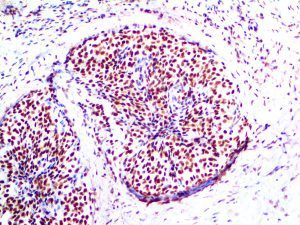

It is the ICU physician who is most likely to witness one of the deadliest manifestations of the abnormal immunological response, the cytokine storm syndrome (CSS). This response is also referred to by some as the cytokine release syndrome (CRS). CSS is characterized by continuous activation and expansion of macrophage and lymphocyte populations, which secrete large amounts of cytokines, causing the cytokine storm. This massive cytokine release is akin to hemophagocytic lymphohistiocytosis (HLH) disease, a syndrome characterized by initial unchecked and persistent activation of cytotoxic T lymphocytes and NK cells.

Clinical and laboratory manifestations of HLH include fever, enlarged liver and/or spleen, neurologic dysfunction, coagulopathy, liver dysfunction, cytopenias (i.e., low levels of erythrocytes, leukocytes, and/or platelets), hypertriglyceridemia, hyperferritinemia, hemophagocytosis, and eventually diminished NK cell activity as the immune system becomes progressively paralyzed. HLH can be familial (primary HLH) or secondary to another disease process (sHLH), such as rheumatic disease, in which it is referred to as macrophage activation syndrome (MAS, characterized by elevated ferritin).